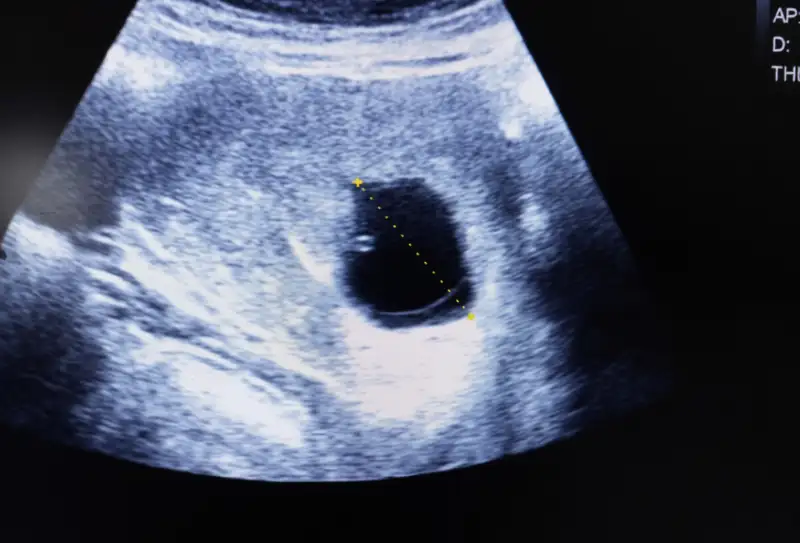

Blighted ovum yang sering disebut juga anembryonic pregnancy atau kehamilan anembrionik, terjadi ketika kantong kehamilan (gestational sac) terbentuk di dalam rahim tapi embrio (janin) tidak berkembang atau sudah berhenti berkembang dan terkadang sudah diserap oleh tubuh. Hormon kehamilan sering tetap naik sehingga tes kehamilan tetap menunjukkan hasil positif sampai pemeriksaan USG menunjukkan tidak ada janin.

Diagnosis biasanya ditegakkan lewat pemeriksaan USG. Kriteria yang sering dipakai, diantaranya :

-Jika tampak kantong kehamilan dengan mean sac diameter (MSD) ≥ 25 mm tanpa embrio, diklasifikasikan sebagai anembryonic pregnancy.

-Atau jika tidak ditemukan embrio pada pemeriksaan tindak lanjut : misalnya ≥11 hari setelah terlihat adanya kantong dengan yolk sac tapi tanpa embrio, atau ≥14 hari setelah pemeriksaan yang hanya menunjukkan kantong tanpa embrio/yolk sac. Dokter akan menggabungkan hasil USG dengan riwayat kehamilan dan kadar hormon (hCG) bila perlu.